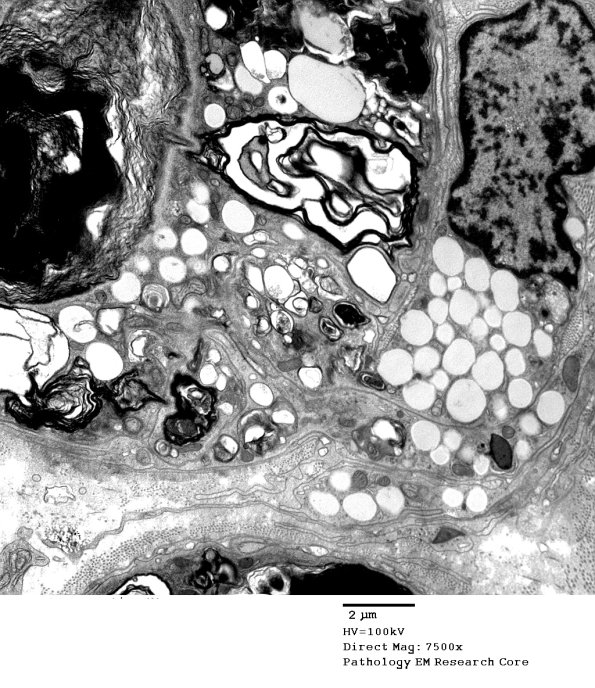

A higher magnification image of a locus of interaction between the macrophage and the Schwann cell.